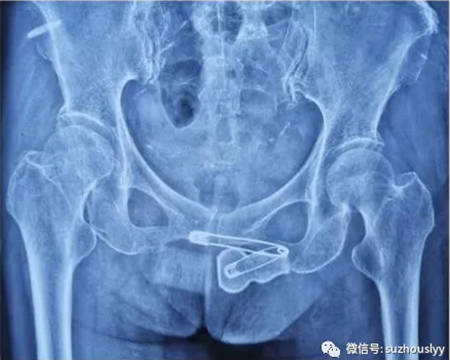

术前X线检查示左侧股骨颈骨折